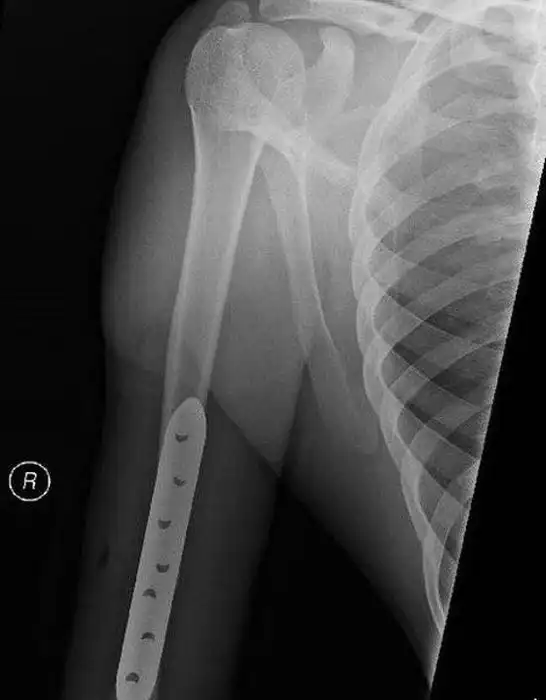

После просмотра этих фотографий вам будет трудно поверить в то, что мотоциклист выжил, всего лишь сломав руку в нескольких местах.